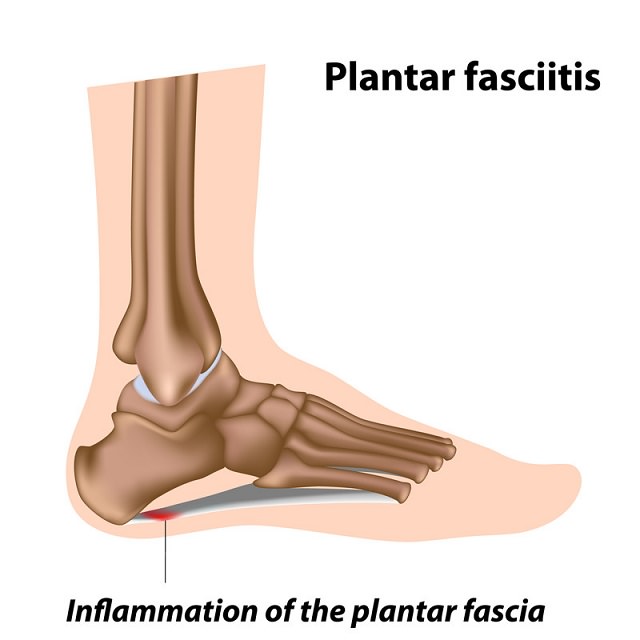

Painful Plantar Fasciitis Ligament Feet Disorder . Study Education